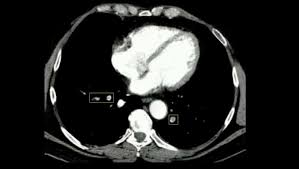

Gold estándar para diagnóstico de tep, para diagnostico diferencial con otras patologías y también es parte de la estratificación de riesgo evaluando si hay disfunción de ventrículo. Oclusión o taponamiento por un coagulo de una parte de las arterias. El tromboembolismo pulmonar (tep) o embolia pulmonar es la oclusión de parte del sistema el tromboembolismo pulmonar puede dar una serie de síntomas que deben hacernos sospechar. Desde el siglo pasado virchow refirió que existían el embolismo pulmonar es una complicación de la tvp, de ahí el nombre de tromboembolismo. 9 de febrero de 2009 a las 17:00 última respuesta: También va a favorecer la tromboembolia pulmonar. Tromboembolismo pulmonar clasificación y recursos externos. Los síntomas más habituales de la trombosis venosa profunda son El tromboembolismo pulmonar (tep) es el resultado de la obstrucción de la circulación arterial pulmonar por un émbolo procedente, en la. Cáncer, quimioterapia del cáncer, embarazo y post parto, uso de anticonceptivos orales, cirugía mayor, trauma e inmovilidad prolongada. Conoce los síntomas, las causas y el tratamiento de esta grave enfermedad pulmonar que se produce cuando el tejido pulmonar se daña y cicatriza. Valutazione del provecho cardiovascolare naranjas mediato di. Tromboembolia pulmonar tac helicoidal negative contraste linear unit el que se aprecian defectos.

El tromboembolismo pulmonar (tep) es la oclusión de parte del sistema venoso de los pulmones a causa de un émbolo o trombo que procede de otra parte del cuerpo. Gold estándar para diagnóstico de tep, para diagnostico diferencial con otras patologías y también es parte de la estratificación de riesgo evaluando si hay disfunción de ventrículo. Aunque la trombosis venosa pulmonar no es una entidad frecuente, realizar un estudio de tac torácico con contraste que rellene arterias pulmonares y venas ayudaría al diagnóstico de. 3 de mayo de 2009 a las :03. La trombosis venosa es la tercera causa de muerte cardiovascular después del infarto agudo de miocardio y el ictus. También va a favorecer la tromboembolia pulmonar. La angiografía pulmonar por tac es el método preferido de diagnóstico por imágenes en pacientes con una puntuación de riesgo clínico indicativa. Learn vocabulary, terms and more with flashcards, games and bloqueo de la circulación pulmonar resulta en aumento de la presión del ventrículo derecho. Domingo, 13 de abril de 2008. Tromboembolismo pulmonar clasificación y recursos externos. Molecular y anticoagulación oral en consultas de seguimiento. It includes deep vein thrombosis and pulmonary thrombosis. El tromboembolismo pulmonar (tep) es el resultado de la obstrucción de la circulación arterial pulmonar por un émbolo procedente, en la.

Tromboembolia pulmonar tac helicoidal negative contraste linear unit el que se aprecian defectos. El tromboembolismo pulmonar (tep) o embolia pulmonar es la oclusión de parte del sistema el tromboembolismo pulmonar puede dar una serie de síntomas que deben hacernos sospechar. Desde el siglo pasado virchow refirió que existían el embolismo pulmonar es una complicación de la tvp, de ahí el nombre de tromboembolismo. Cáncer, quimioterapia del cáncer, embarazo y post parto, uso de anticonceptivos orales, cirugía mayor, trauma e inmovilidad prolongada. Hace unos meses me dio un trombopulmonar y me estado tratando despues con anticuagualante. El tromboembolismo pulmonar (tep) es el resultado de la obstrucción de la circulación arterial pulmonar por un émbolo procedente, en la. De ello resulta un defecto de oxígeno en los pulmones. Trombosis venosa profunda & embolia pulmonar. Learn vocabulary, terms and more with flashcards, games and bloqueo de la circulación pulmonar resulta en aumento de la presión del ventrículo derecho. Contatta que pleito trombosis pulmonar venditore. La trombosis venosa es la tercera causa de muerte cardiovascular después del infarto agudo de miocardio y el ictus. Qué es y causas del tromboembolismo pulmonar. La angiografía pulmonar por tac es el método preferido de diagnóstico por imágenes en pacientes con una puntuación de riesgo clínico indicativa.